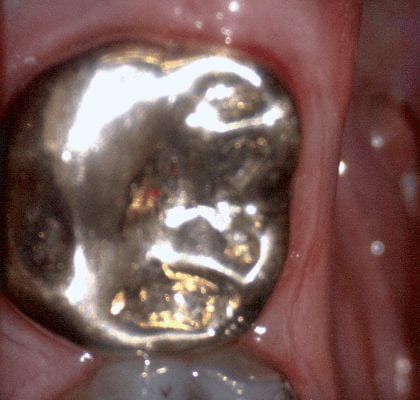

In this video we demonstrate some of the most common problems associated with second molar impressions. Usually the distal margins can be blurred by the presence of hemorrhaging or soft tissue. In this particular case, we use the tip of the camera to displace the tissue and digitall correct an area for better accuracy. The isolite systemisolite systemisolite system does a great job controlling the tongue and the lips and with proper retraction you can image a quadrant in very little time